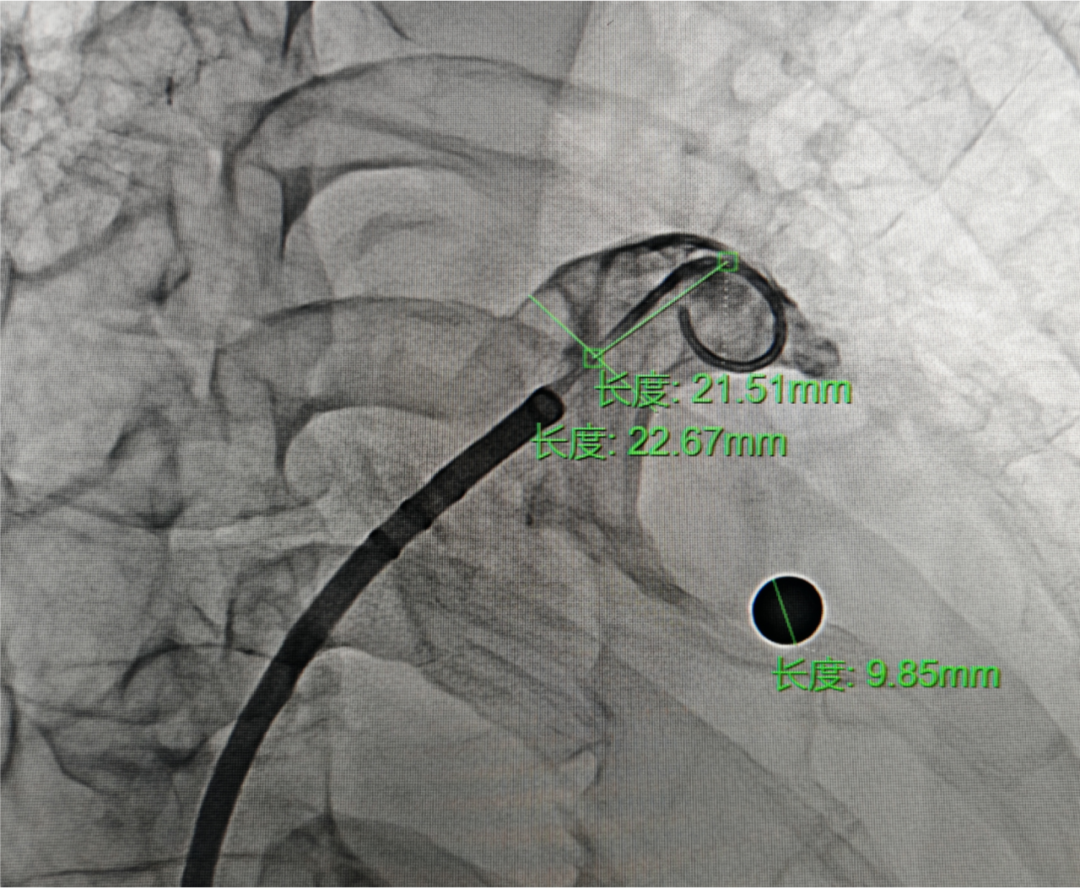

DSA下右肩位造影+测量

右肩位测量,开口22.67 mm,深度21.51 mm

封堵策略:术前CT报告为“风向袋型”左心耳。术中DSA肝位造影测量开口26.13mm,可用深度29.65mm;DSA右肩位造影测量开口22.67mm,深度21.51mm,心耳为“鸡翅型”左心耳,深度空间充分,综合考虑选择MemoLefort LAFDQ-29封堵器,退鞘法展开封堵器,保证封堵器稳定释放。

术中DSA肝位造影测量开口26.13mm,可用深度29.65mm;DSA右肩位造影测量开口22.67mm,深度21.51mm,心耳为“鸡翅型”左心耳,深度空间充分,综合考虑选择MemoLefort LAFDQ-29封堵器;MemoLefort封堵器远端为花苞型内扣保护,顺应性强,阻流膜高度覆盖,能更好适应心耳(包括浅心耳)内部结构及形态,达到稳定锚定。